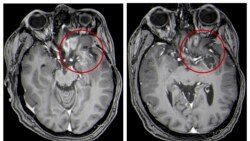

This combination of MRI images provided by the University of Alabama in April 2021 shows scans of a child with a brain tumor, before and after the treatment.

Average survival was just over a year. That is more than two times longer than in the past. As of last June, four of the patients were still alive at least 18 months after treatment.

Tests also showed high levels of specialized immune system cells in their tumors. This suggests that the treatment had created help needed from the body to attack the disease. No serious safety issues were seen.